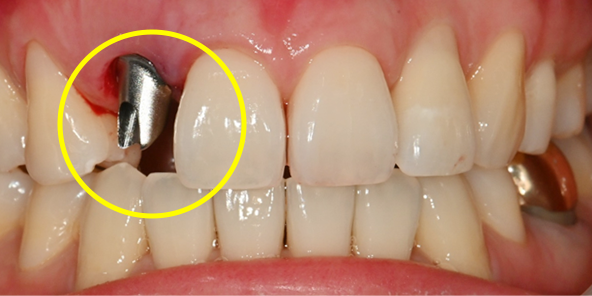

Surgery Day: Precisely as Planned

Guide-Based Implant Placement

The critical phase that minimizes unnecessary error and connects the prosthesis on the same day.

Before Treatment

After extraction, precise placement using surgical guide followed by pre-fabricated abutment connection

After extraction, precise placement using surgical guide,

followed by connection of

pre-fabricated abutment

Prosthesis completed on the day of surgery

Prosthesis completed on surgery day

After 2 months, replaced with final prosthesis if gingival contour changes or as needed

After 2 months, if gingival contour changes

or as needed, replaced with final prosthesis